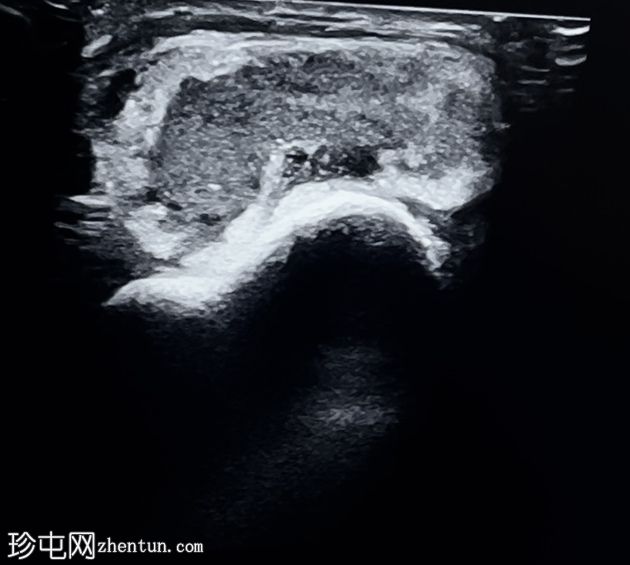

超声

横断面

斜位

超声显示胸锁关节内有异质性低回声区,内含碎屑,周围软组织炎症,符合积液的影像学表现。